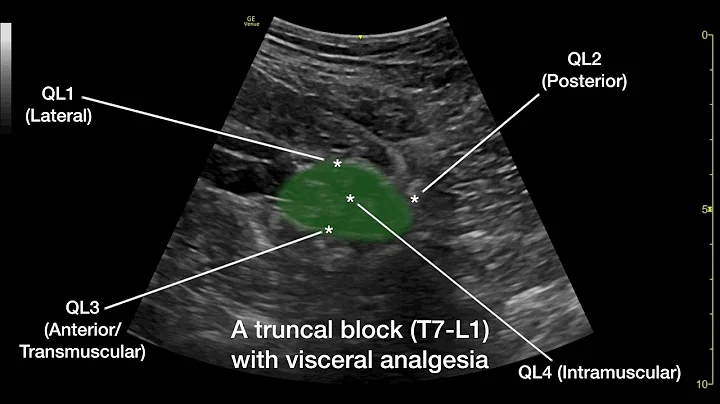

In this video we discuss the anterior approach to the quadratus lumborum block (also known as QL3, or the transmuscular